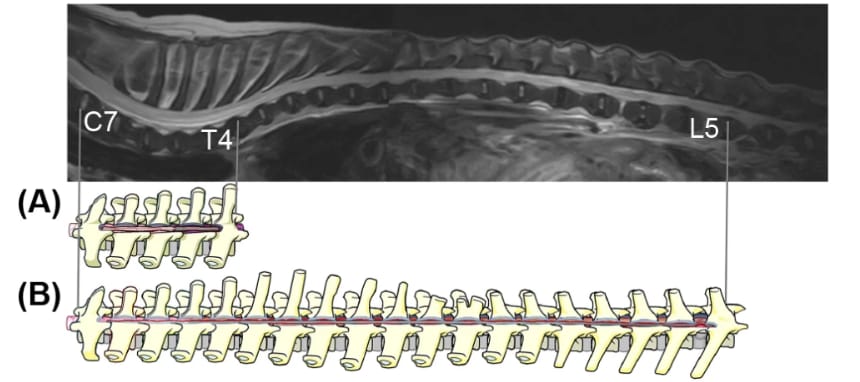

Schematic depiction comparing EHLD-L with that after EHLD performed hypothetically in the same dog. Surgical image of an EHLD-L method in a dog (no. 5). (A) EHLD-L was performed from the site of the cranial region with intramedullary hyperintensity on T2W-MRI toward the caudal site until the spinal cord with swelling or softening was visible (C7–T4). (B) If EHLD, as previously reported, is applied, spinal decompression from C7 to L5 is required